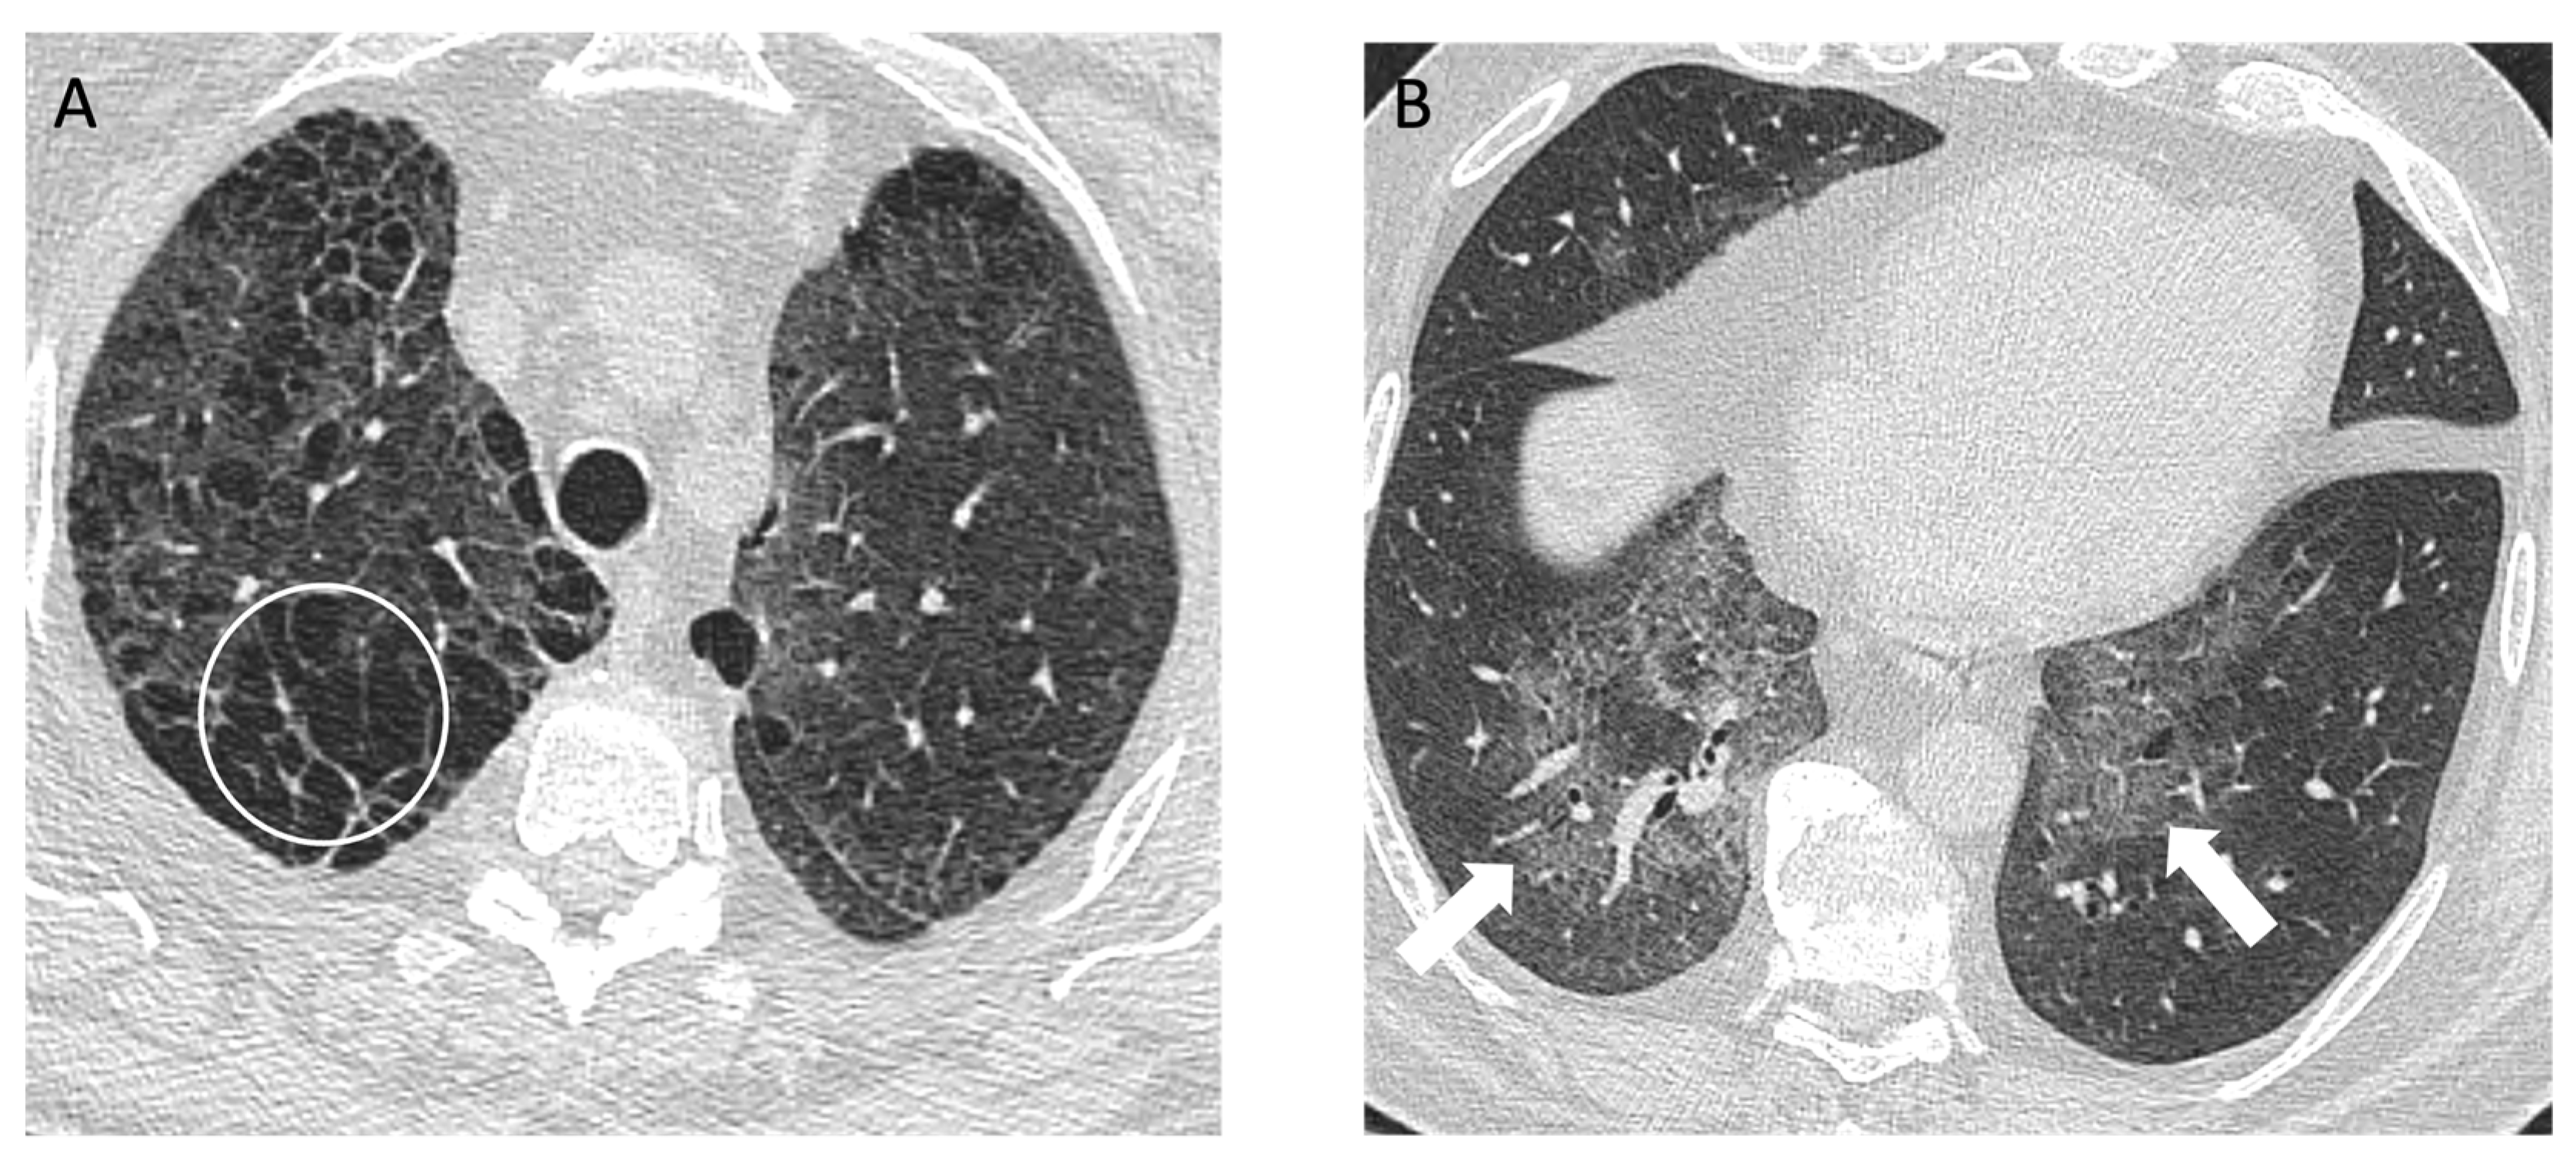

4.2. Coal Worker’s Pneumoconiosis

| Hard Metal Lung Disease | Constrictive bronchiolitis, mosaic lung attenuation, air trapping, fibrosis with traction bronchiectasis [55,56] | Difficult to differentiate by imaging only; evidence of intersitial lung disease along with clinical history and histological examination supports diagnosis [55,56] |